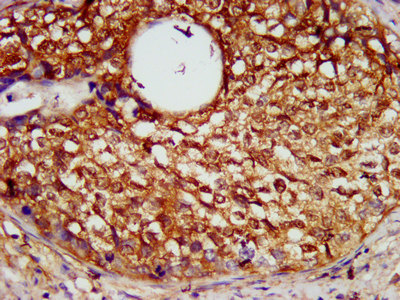

IHC image of CSB-PA021072LA01HU diluted at 1:600 and staining in paraffin-embedded human pancreatic cancer performed on a Leica BondTM system. After dewaxing and hydration, antigen retrieval was mediated by high pressure in a citrate buffer (pH 6.0). Section was blocked with 10% normal goat serum 30min at RT. Then primary antibody (1% BSA) was incubated at 4°C overnight. The primary is detected by a biotinylated secondary antibody and visualized using an HRP conjugated SP system.